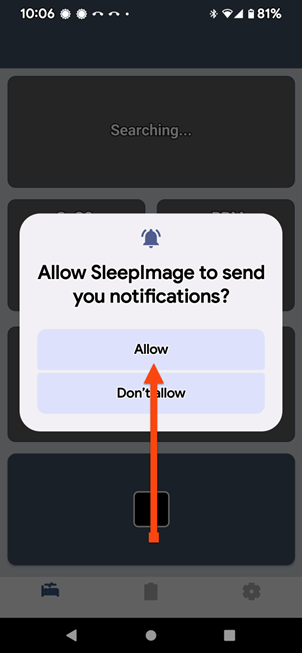

SLEEPIMAGE APP (Android)

SLEEPIMAGE APP (Android)

SLEEPIMAGE APP (Android)

SLEEPIMAGE APP (Android)

SLEEPIMAGE APP (Android)

SLEEPIMAGE APP (Android)

SLEEPIMAGE APP (Android)

SLEEPIMAGE APP (Android)

SLEEPIMAGE APP (Android)

SLEEPIMAGE APP (Android)

SLEEPIMAGE APP (Android)

SLEEPIMAGE APP (Android)

SLEEPIMAGE APP (Android)

SLEEPIMAGE APP (Android)

SLEEPIMAGE APP (Android)

SLEEPIMAGE APP (Android)

SLEEPIMAGE APP (Android)

SLEEPIMAGE APP (Android)

SLEEPIMAGE APP (Android)

SLEEPIMAGE APP (Android)

SLEEPIMAGE APP (iPhone)

SLEEPIMAGE APP (Android)

SLEEPIMAGE APP (Android)

SLEEPIMAGE APP (Android)

SLEEPIMAGE APP (Android)

SLEEPIMAGE APP (Android)

SLEEPIMAGE APP (Android)

SLEEPIMAGE APP (Android)

SLEEPIMAGE APP (Android)